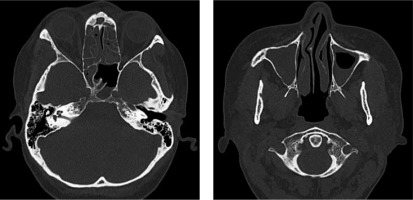

In June 2017, a nonsmoker 48-year-old woman with a history of persistent bronchial asthma and chronic pansinusitis was diagnosed with respiratory failure in the course of hypereosinophilic syndrome. Computed tomography (CT) of the chest showed massive interstitial infiltrates and laboratory tests revealed eosinophilia (8286 cells/µl). Therapy with systemic and inhaled glucocorticoids and inhaled bronchodilators was started, with moderate improvement. Further workup displayed elevated level of eosinophils (8%) in bronchoalveolar lavage (BAL) fluid and negative antinuclear and antineutrophil cytoplasmic antibodies. Previous attempts to taper oral GS led to flare of the disease; therefore the patient had add-on therapy with the humanized anti-IL-5 monoclonal antibody mepolizumab for several months (last dose was given in May 2019). However, instead of the applied treatment and normal level of peripheral eosinophils (< 500 cells/µl) she presented with fluctuating lower respiratory tract symptoms (wheezing, rhonchi, cough, dyspnea), recurrent exacerbations of pansinusitis with persisting hearing impairment (Fig. 1). In July 2019 functional endoscopic sinus surgery was performed, revealing eosinophilic (approx. 10% of the cells) chronic infiltrates of the mucosal stroma.